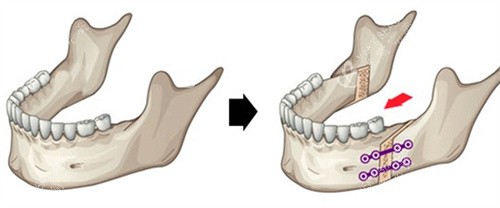

王芳医生给他的方案是"上颌前徙术":从口腔内切个小口,把上颌骨整体前移3mm。手术用了2小时,出血量不到50ml。术后第5天,小凯就能吃面条;***0天,他已经敢对着镜子咧嘴笑了。